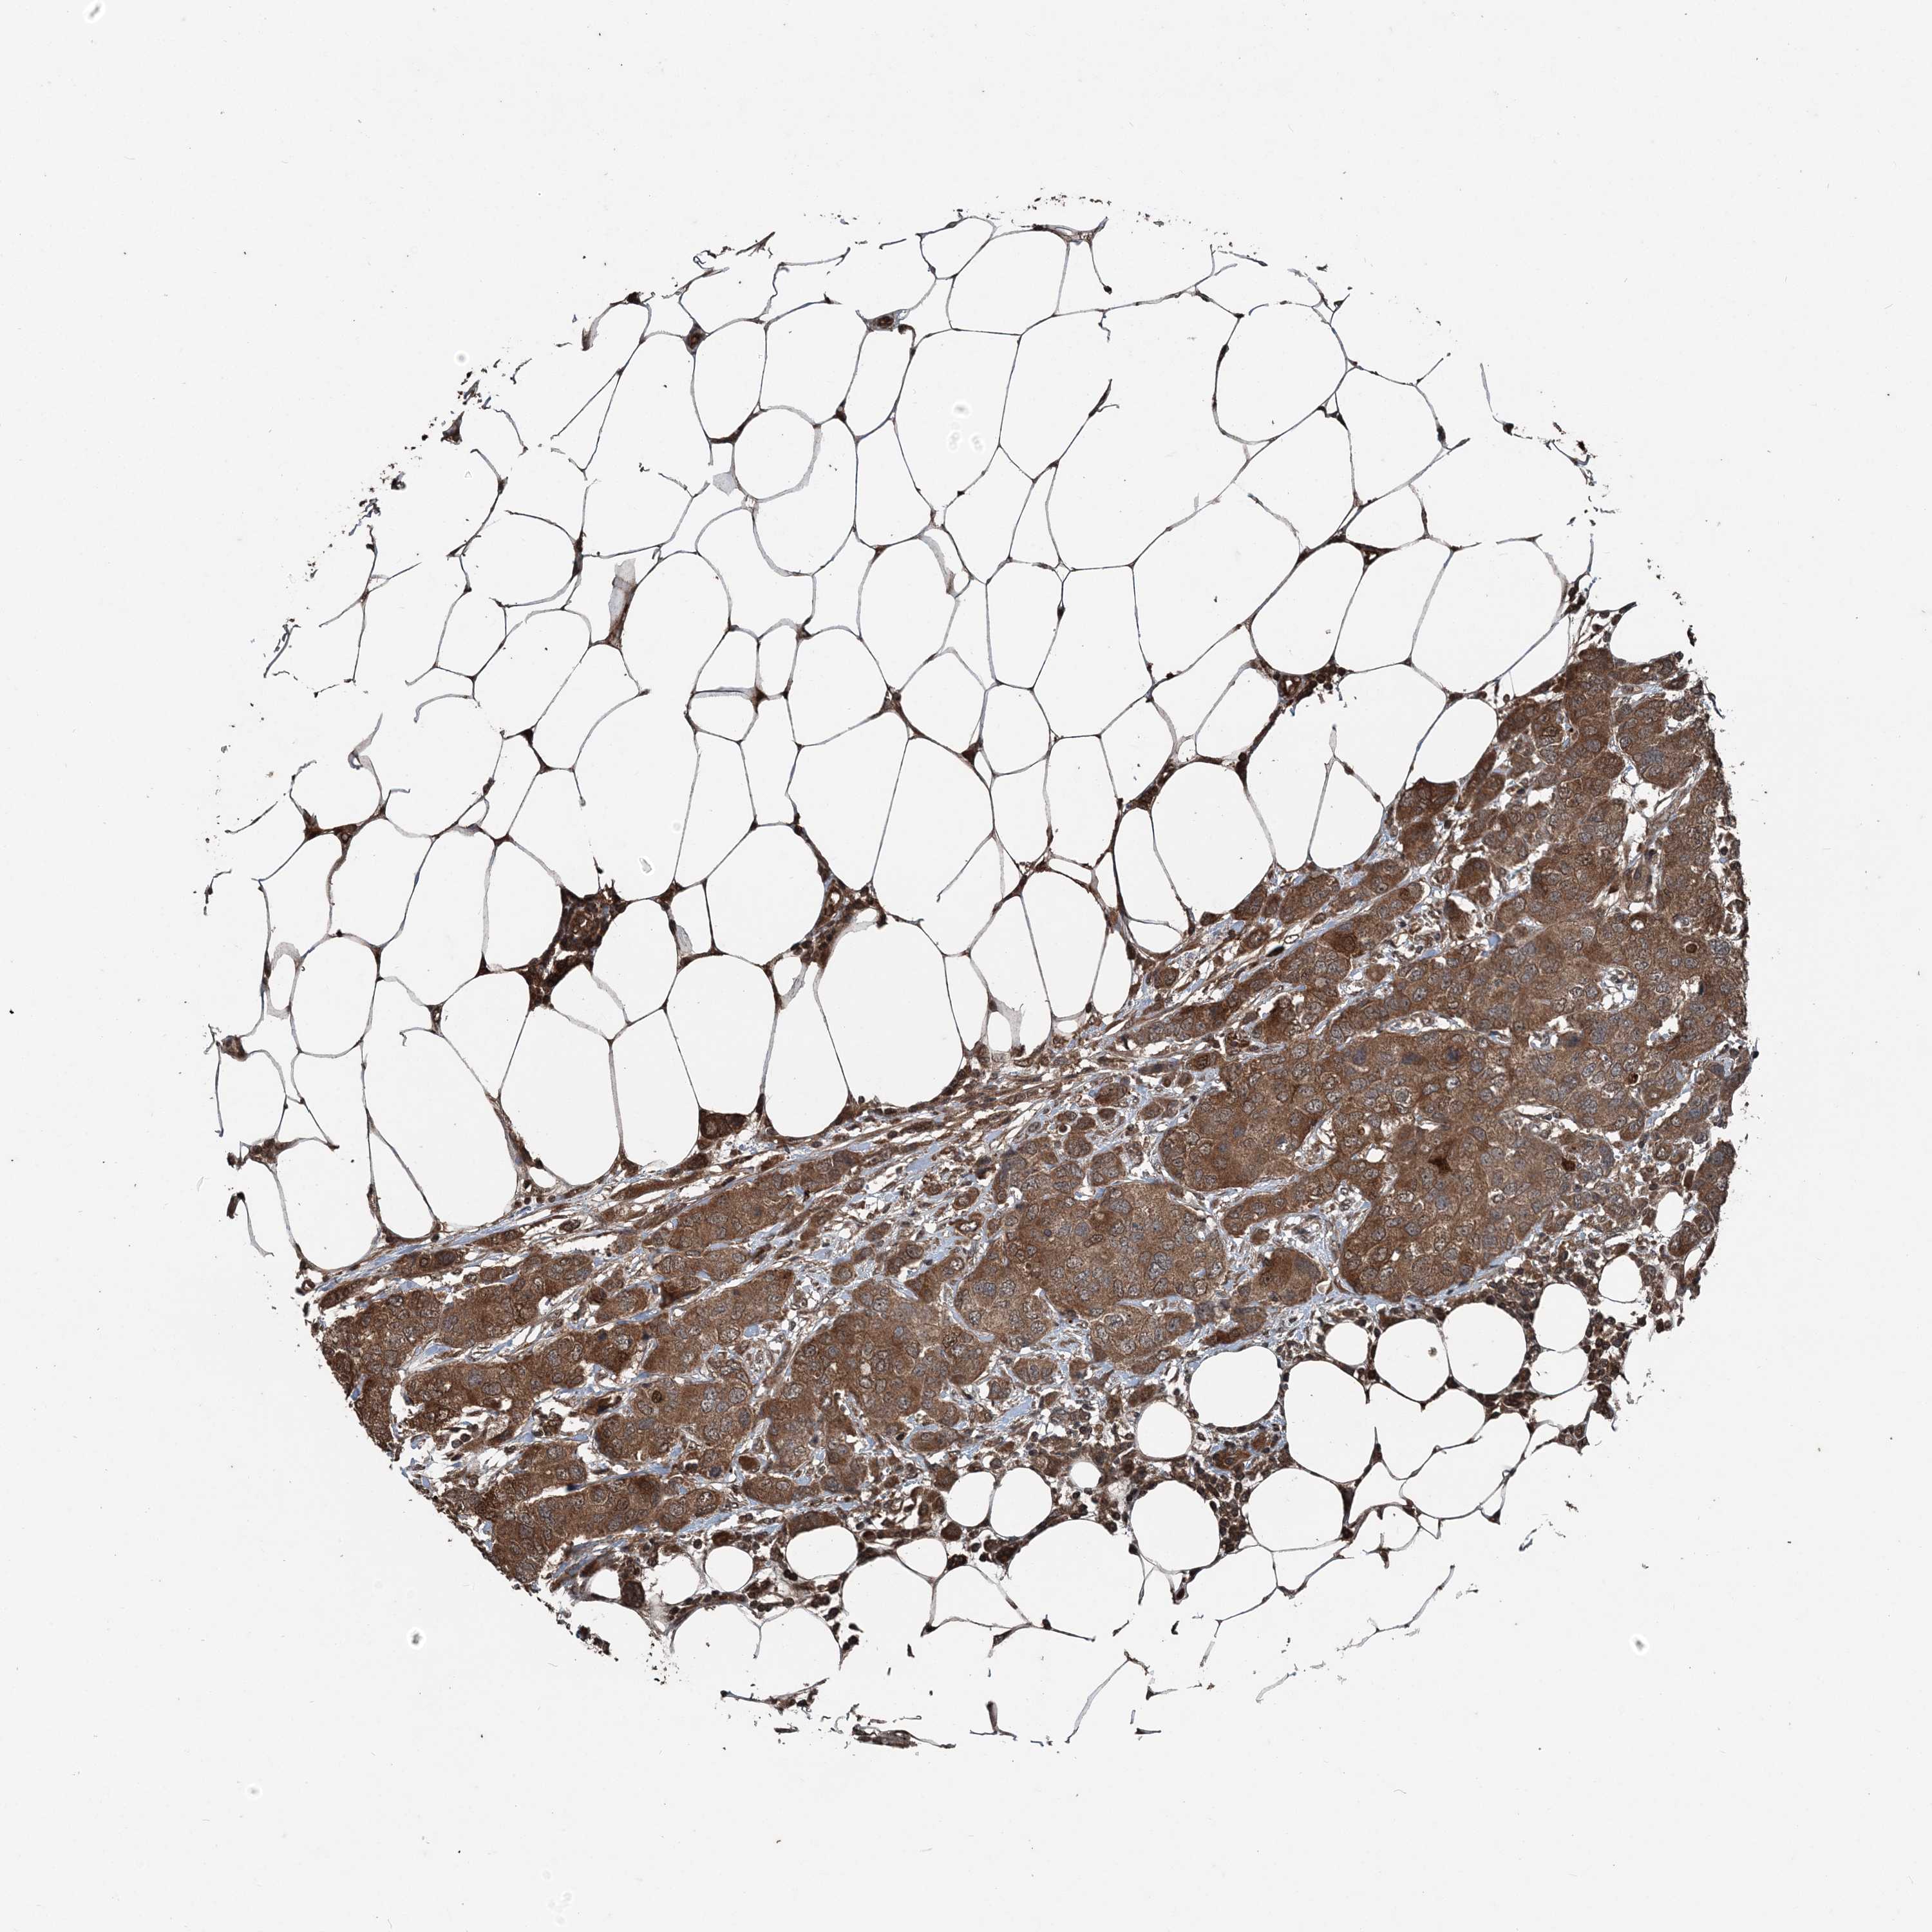

CANCER BREAST CANCER Show tissue menu

BRCA TCGA BRCA VALIDATION PROTEIN EXPRESSION

ANTIBODIES

AND

VALIDATION